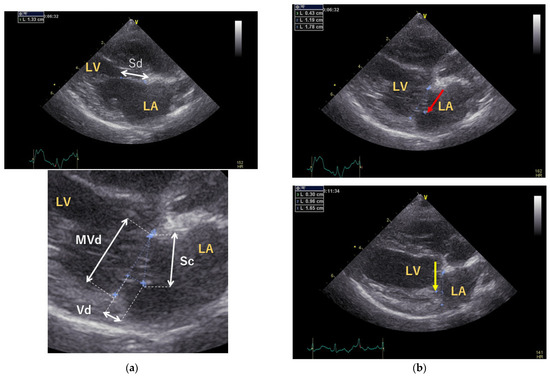

Preoperative and postoperative assessments included measurement of vertebral heart size (VHS) by thoracic radiography and evaluation of the E and A waves, left atrial-to-aortic diameter ratio (LA/Ao), and body weight-normalized end-diastolic left ventricular diameter (LVIDdN) by echocardiography using a 6 or 12 MHz phased-array transducer (Vivid E9; GE Healthcare Co., Ltd., Tokyo, Japan). In addition, the septal leaflet lengths were measured at coaptation (Sc) and end-diastole (Sd) to calculate the coaptation length (CL): CL = Sd−Sc. The CL-index was calculated by dividing CL by the mitral valve short-axis dimension (MVd) at the end-systole. The vertical distance between the annular line and the closing point (Vd) at the end-systole was measured for evaluation of the CT length (Figure 1) [15]. The Vd was measured with the left atrial side set to negative and the left ventricular side set to positive.

The heart size was significantly reduced, and the CL-index was significantly improved (Table 2): LA/Ao was 2.21 ± 0.37 preoperatively and 1.29 ± 0.16 postoperatively (p < 0.01), and LVIDdN was 2.14 ± 0.18 preoperatively and 1.49 ± 0.21 postoperatively (p < 0.01). After MODEL surgery, the E wave decreased from 1.22 ± 0.35 m/s to 0.89 m/s (0.57–1.06 m/s), and the A wave increased from 0.89 ± 0.26 m/s to 1.16 ± 0.18 m/s; however, the differences were not significant (p = 0.172 and p = 0.159, respectively). In addition, the MVd decreased from 2.07 ± 0.26 cm to 1.26 ± 0.21 cm (p < 0.001); Vd decreased from −0.31 ± 0.11 cm to 0.31 ± 0.16 cm (p < 0.001). Although the CL-index significantly improved from 0.09 ± 0.07 to 0.19 ± 0.08 (p = 0.028), CL was 0.17 ± 0.13 preoperatively and 0.32 ± 0.13 postoperatively, these differences were not significant (p = 0.076).

Figure 1. Echocardiographic assessment of mitral valve morphology. (a) The septal leaflet lengths were measured at end-diastole (Sd) and coaptation (Sc) using a right parasternal four-chamber view. The coaptation length (CL) was calculated using the following formula: CL = Sd-Sc. The CL-index was calculated by dividing the CL by the mitral valve short-axis dimension (MVd) at the end-systole. The vertical distance between the annular line and the closing point (Vd) at the end-systole. The Vd was measured with the left atrial side set to negative and the left ventricular side set to positive. (b) The upper and lower figures show the mitral coaptation of the end-systolic mitral valve before and after surgery. After surgery, the mitral valve height (red arrow) was reduced, and mitral valve coaptation was seen in the left ventricle (yellow arrows). LA: left atrium; LV: left ventricle; Sd: septal leaflet length at end-diastole; Sc: septal leaflet length at coaptation; CL: coaptation length; MVd: mitral valve short-axis dimension at end-systole; Vd: vertical distance between annular line and closing point at end-systole.